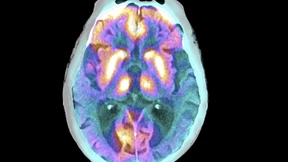

Wenn nichts passiert, könnten im Jahr 2050 mehr als 2,5 Millionen Menschen in Deutschland an Demenz leiden. Forscher wollen nun individuelle Risikoprofile erstellen, um die Prävention zu verbessern.

Fast zwei Millionen Menschen in Deutschland leben mit Demenz. Das große Vergessen ist der Angstmacher der späten Jahre. Doch es gibt neue Behandlungsmethoden.